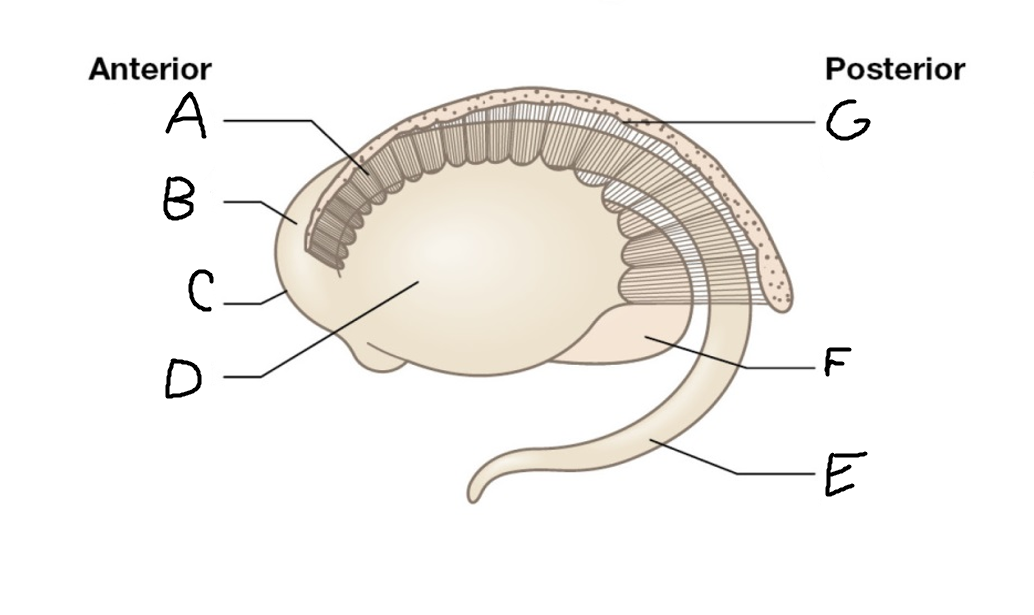

A

internal capsule (anterior limb)

B

caudate nucleus body

C

caudate nucleus head

D

putamen

E

caudate nucleus tail

F

thalamus

G

internal capsule (posterior limb)